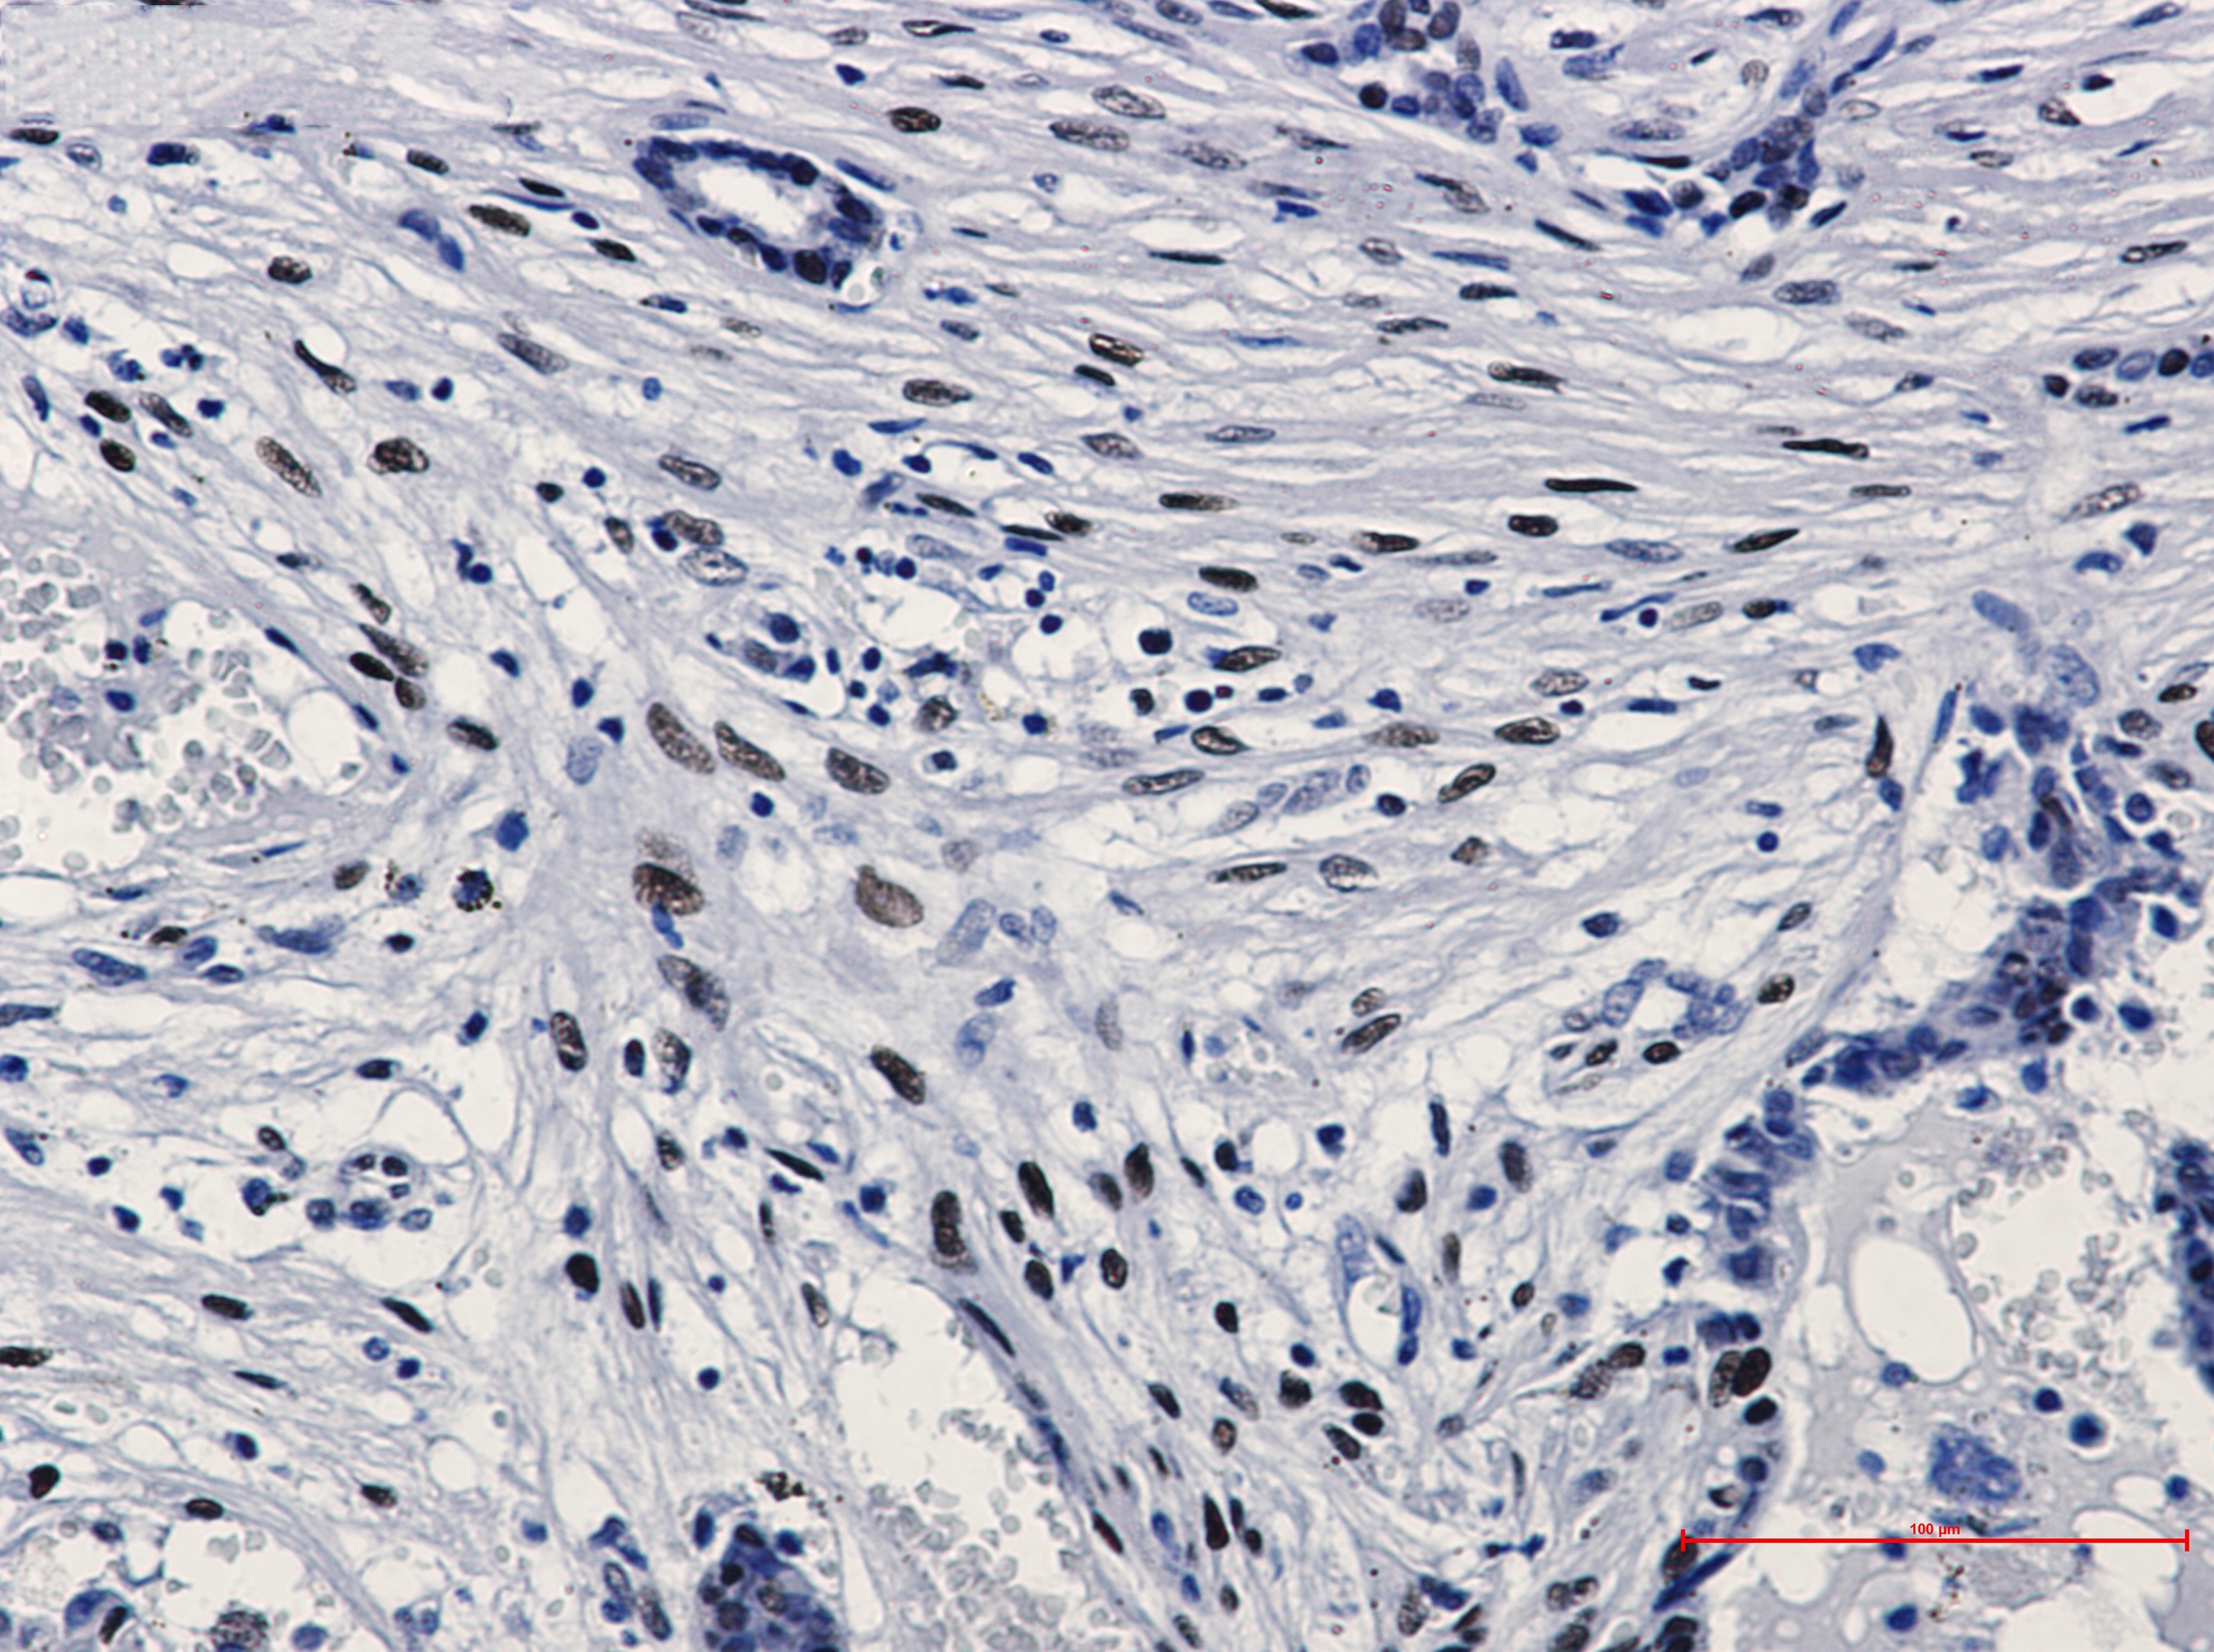

Immunohistochemistry of c-Jun (phospho S63) in paraffin-embedded Human breast cancer tissue using c-Jun (phospho S63) Rabbit mAb at dilution 1/20